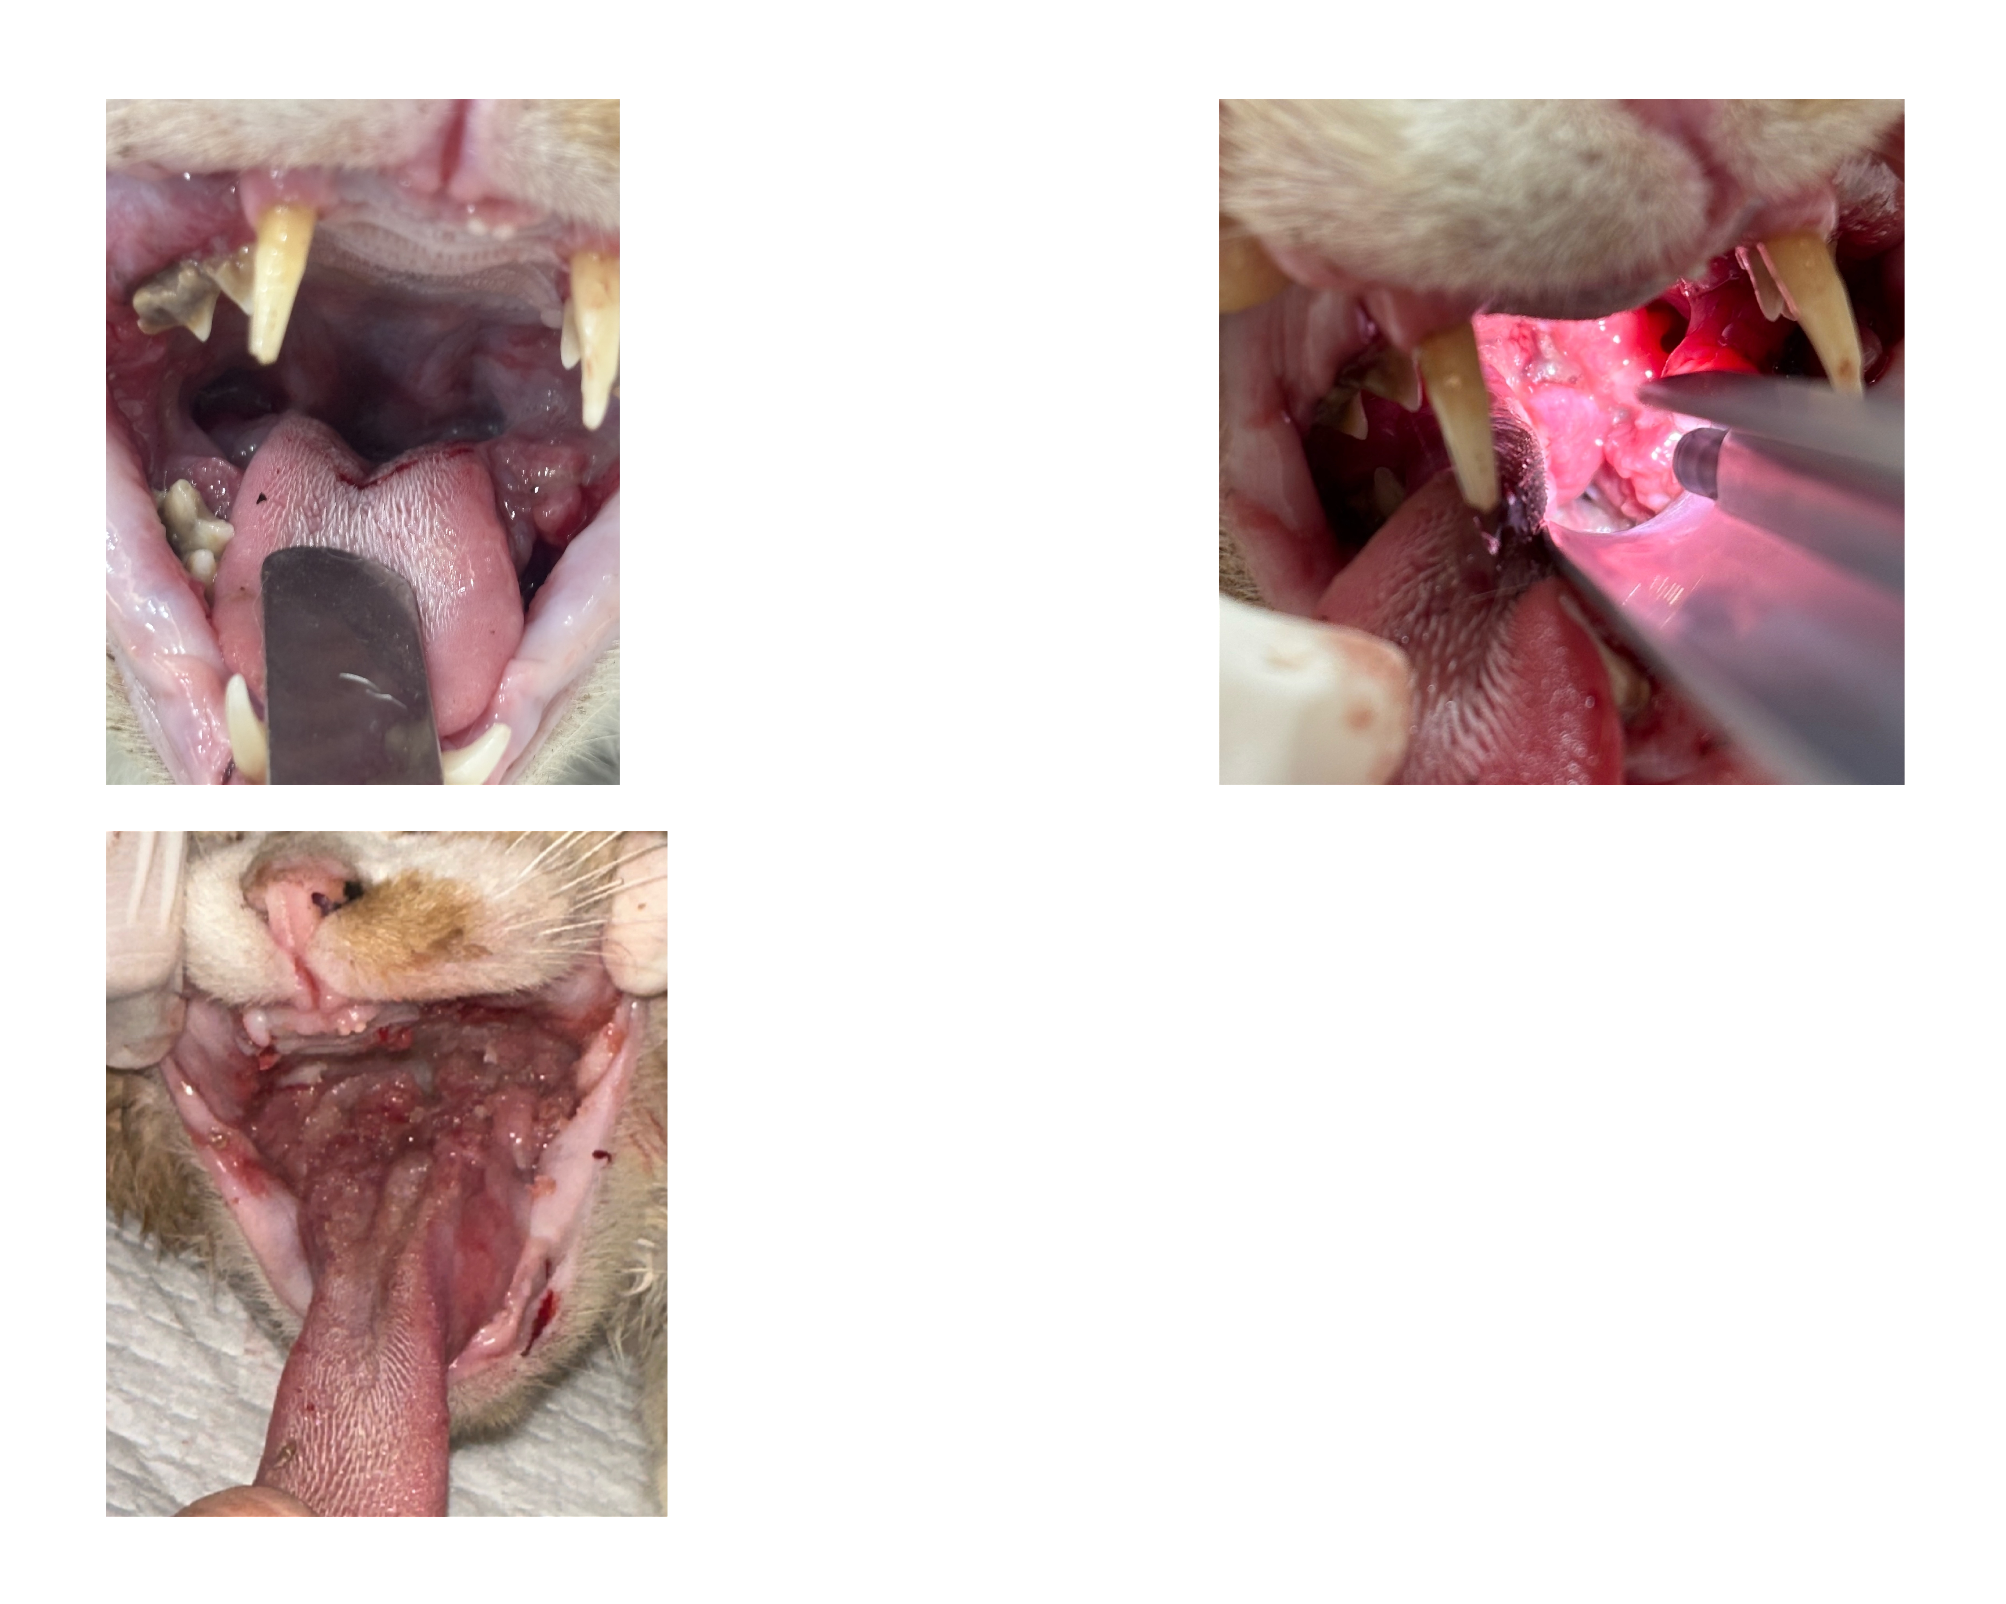

| 치료과정 | 호빵이는 저녁에도 습식을 먹으러 매일 나오지는 않던 녀석이라 구조가 걱정이었습니다. 습식 시간에 나타나길 기다리다가 한 차례 구조에 실패해 마음을 졸이게 했지만, 겨울집이나 여름집을 마련해 두는 곳에는 잘 머무르곤 했기에 이튿날인 10월 21일(화) 낮에 급식소와 집을 마련해 둔 곳 근처에 포획틀을 설치했고 무사히 구조할 수 있었습니다. 미리 연락해 둔 병원으로 곧바로 이동하였고, 사납고 사람 손을 타지 않는 성격인 터라 마취한 후 대기 시간을 가진 후 본격적인 검사에 들어갔습니다. 이 병원에서는 마취 후 상태를 보고 발치가 필요한지 아닌지를 판단한다고 하였는데요, 호빵이는 오랫동안 구내염을 앓아 왔기에 전발치가 필요한 상태임을 진단받았습니다. 그렇게 당일 모든 이빨에 대한 전발치를 진행하였고, 특히 목 안쪽에 염증이 심했던 상태라 조금 편하게 호흡을 할 수 있도록 추가적인 처치를 해 주셨다고 했습니다. 또 2주 동안 효과가 지속되는 항생제 처치도 진행하였습니다. 불행 중 다행히도 혈액 검사 결과 별다른 문제는 더 발견되지 않았습니다. 병원 방침상 발치 후 당일 퇴원한다고 하였으나, 힘든 수술을 한 아이를 바로 방사할 수는 없어 하루 동안 입원을 부탁드렸고 다음 날인 10월 22일(수) 오전에 호빵이를 데려와 원래 지내던 곳에 제자리 방사하였습니다. |

| 대상묘 치료중 사진 | ![]() ![]() ![]() ![]() |

[치료 전 사진]

[치료 중 사진]